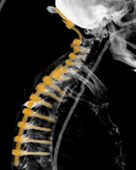

Im Zentrum für Wirbelsäulenchirurgie und Schmerztherapie wird das gesamte Behandlungsspektrum bei Erkrankungen, Unfällen und Schmerzsyndromen der Hals-, Brust- und Lendenwirbelsäule sowie der angrenzenden Strukturen bei Kindern und Erwachsenen in interdisziplinärer Vorgehensweise abgedeckt. Rund um die Uhr besteht die Möglichkeit der Maximalversorgung. Häufig erfolgt die Therapie nach einem Stufenschema, bei dem versucht wird, mit weniger eingreifenden Maßnahmen zu beginnen. Je eingreifender die Therapie, umso höher ein theoretisches Risiko des Auftretens negativer Nebeneffekte.

Insgesamt steht die Behandlung von Verschleißerkrankungen im Vordergrund. Des Weiteren werden im Zentrum jegliche Arten von z. B. Unfällen, Infektionen, Tumoren und Metastasen, Deformitäten, rheumatischen und angeborenen Erkrankungen bei Erwachsenen und Kindern behandelt. Jährlich erfolgen neben den konservativen mehr als 15.000 interventionelle Maßnahmen sowie mehr als 3.000 Operationen. Wenn möglich werden minimalinvasive oder bewegungserhaltende Verfahren angewendet.